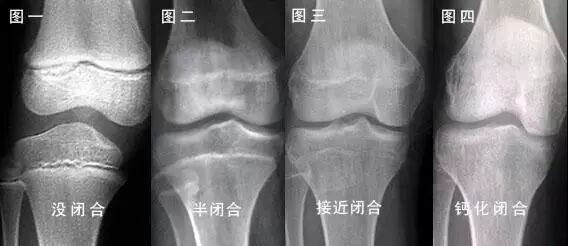

通常认为,人的身高与「骨骺闭合」有关,也就是说骨头不再延长了,一辈子就都这么长了。任何促进骨头延长的方法,只能在骨骺闭合前进行,之后就没办法了。

与身高有关的骨头,主要是我们的腿骨。其中,大腿的股骨上端骨骺,一般在17-19岁闭合,会有2年左右的浮动范围。通常女性比男性早1—3年闭合,所以女孩早长高,也早停长。